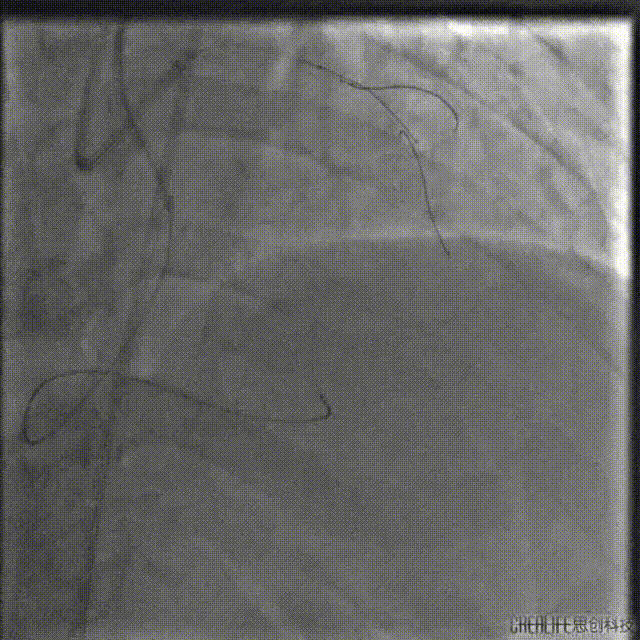

启动逆向开通

考虑间隔支侧枝纤细且存在显著成角迂曲,选择1.5F HighTrack微导管作为逆向微导管,支撑SION导丝进入侧枝。

SION导丝受限于严重迂曲无法通过,遂更换为SUOH 03导丝,通过侧枝走行至LAD闭塞处后反向前送至LAD远段,HighTrack微导管通过侧枝跟进至分叉处。

逆向导丝更换为P200后仍不能突破CTO远端纤维帽至LAD近段,遂调整前向导丝Kissing逆向导丝进入间隔支,送入1.5mm球囊扩张LAD至间隔支。

试图用SUOH03 逆向Knuckle至LAD近段未成功,遂将SUOH03导丝推送至LAD远段。